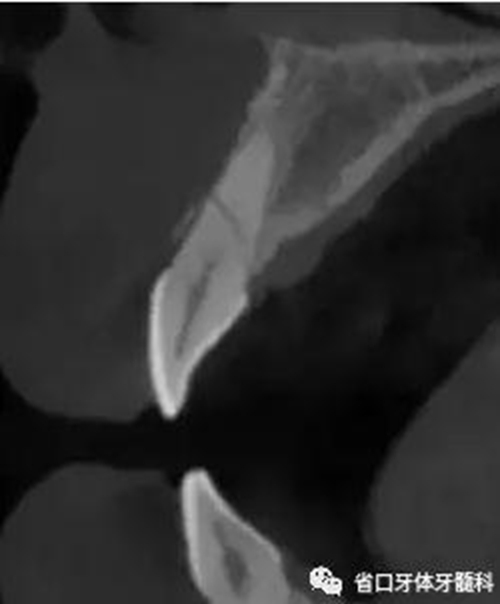

圖4:21術前

CBCT:11、21頸部以下均見一完全性折裂線,兩牙折裂線均位于頜骨內(nèi)且斷端移位不明顯,相應唇側(cè)骨板亦見斷裂且輕度移位。